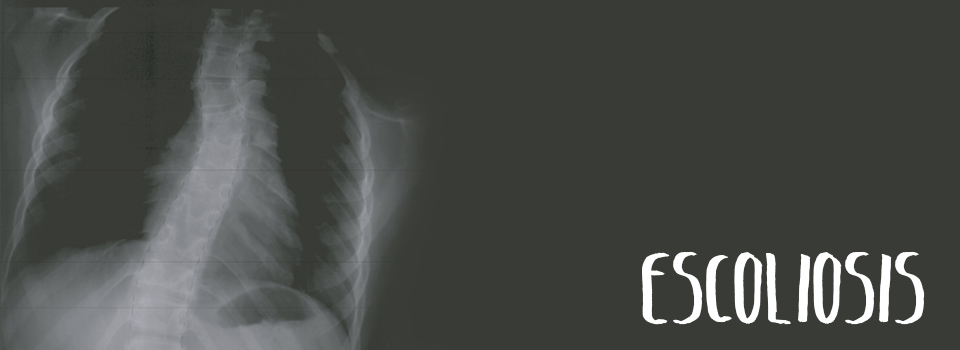

Escoliosis

Es una desviación lateral anormal de la columna vertebral.

La curvatura espinal que se encuentra en la escoliosis puede ser leve y pasar desapercibida, como también severa.

La escoliosis, en condiciones extremas, puede producir dolor de espalda, fatiga y problemas respiratorios.